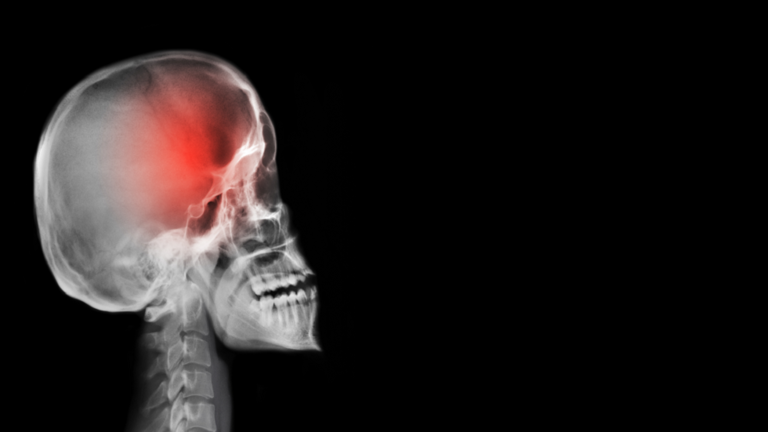

خمس علامات رئيسية تدل أن الصداع قد يكون علامة على وجود ورم في المخ!